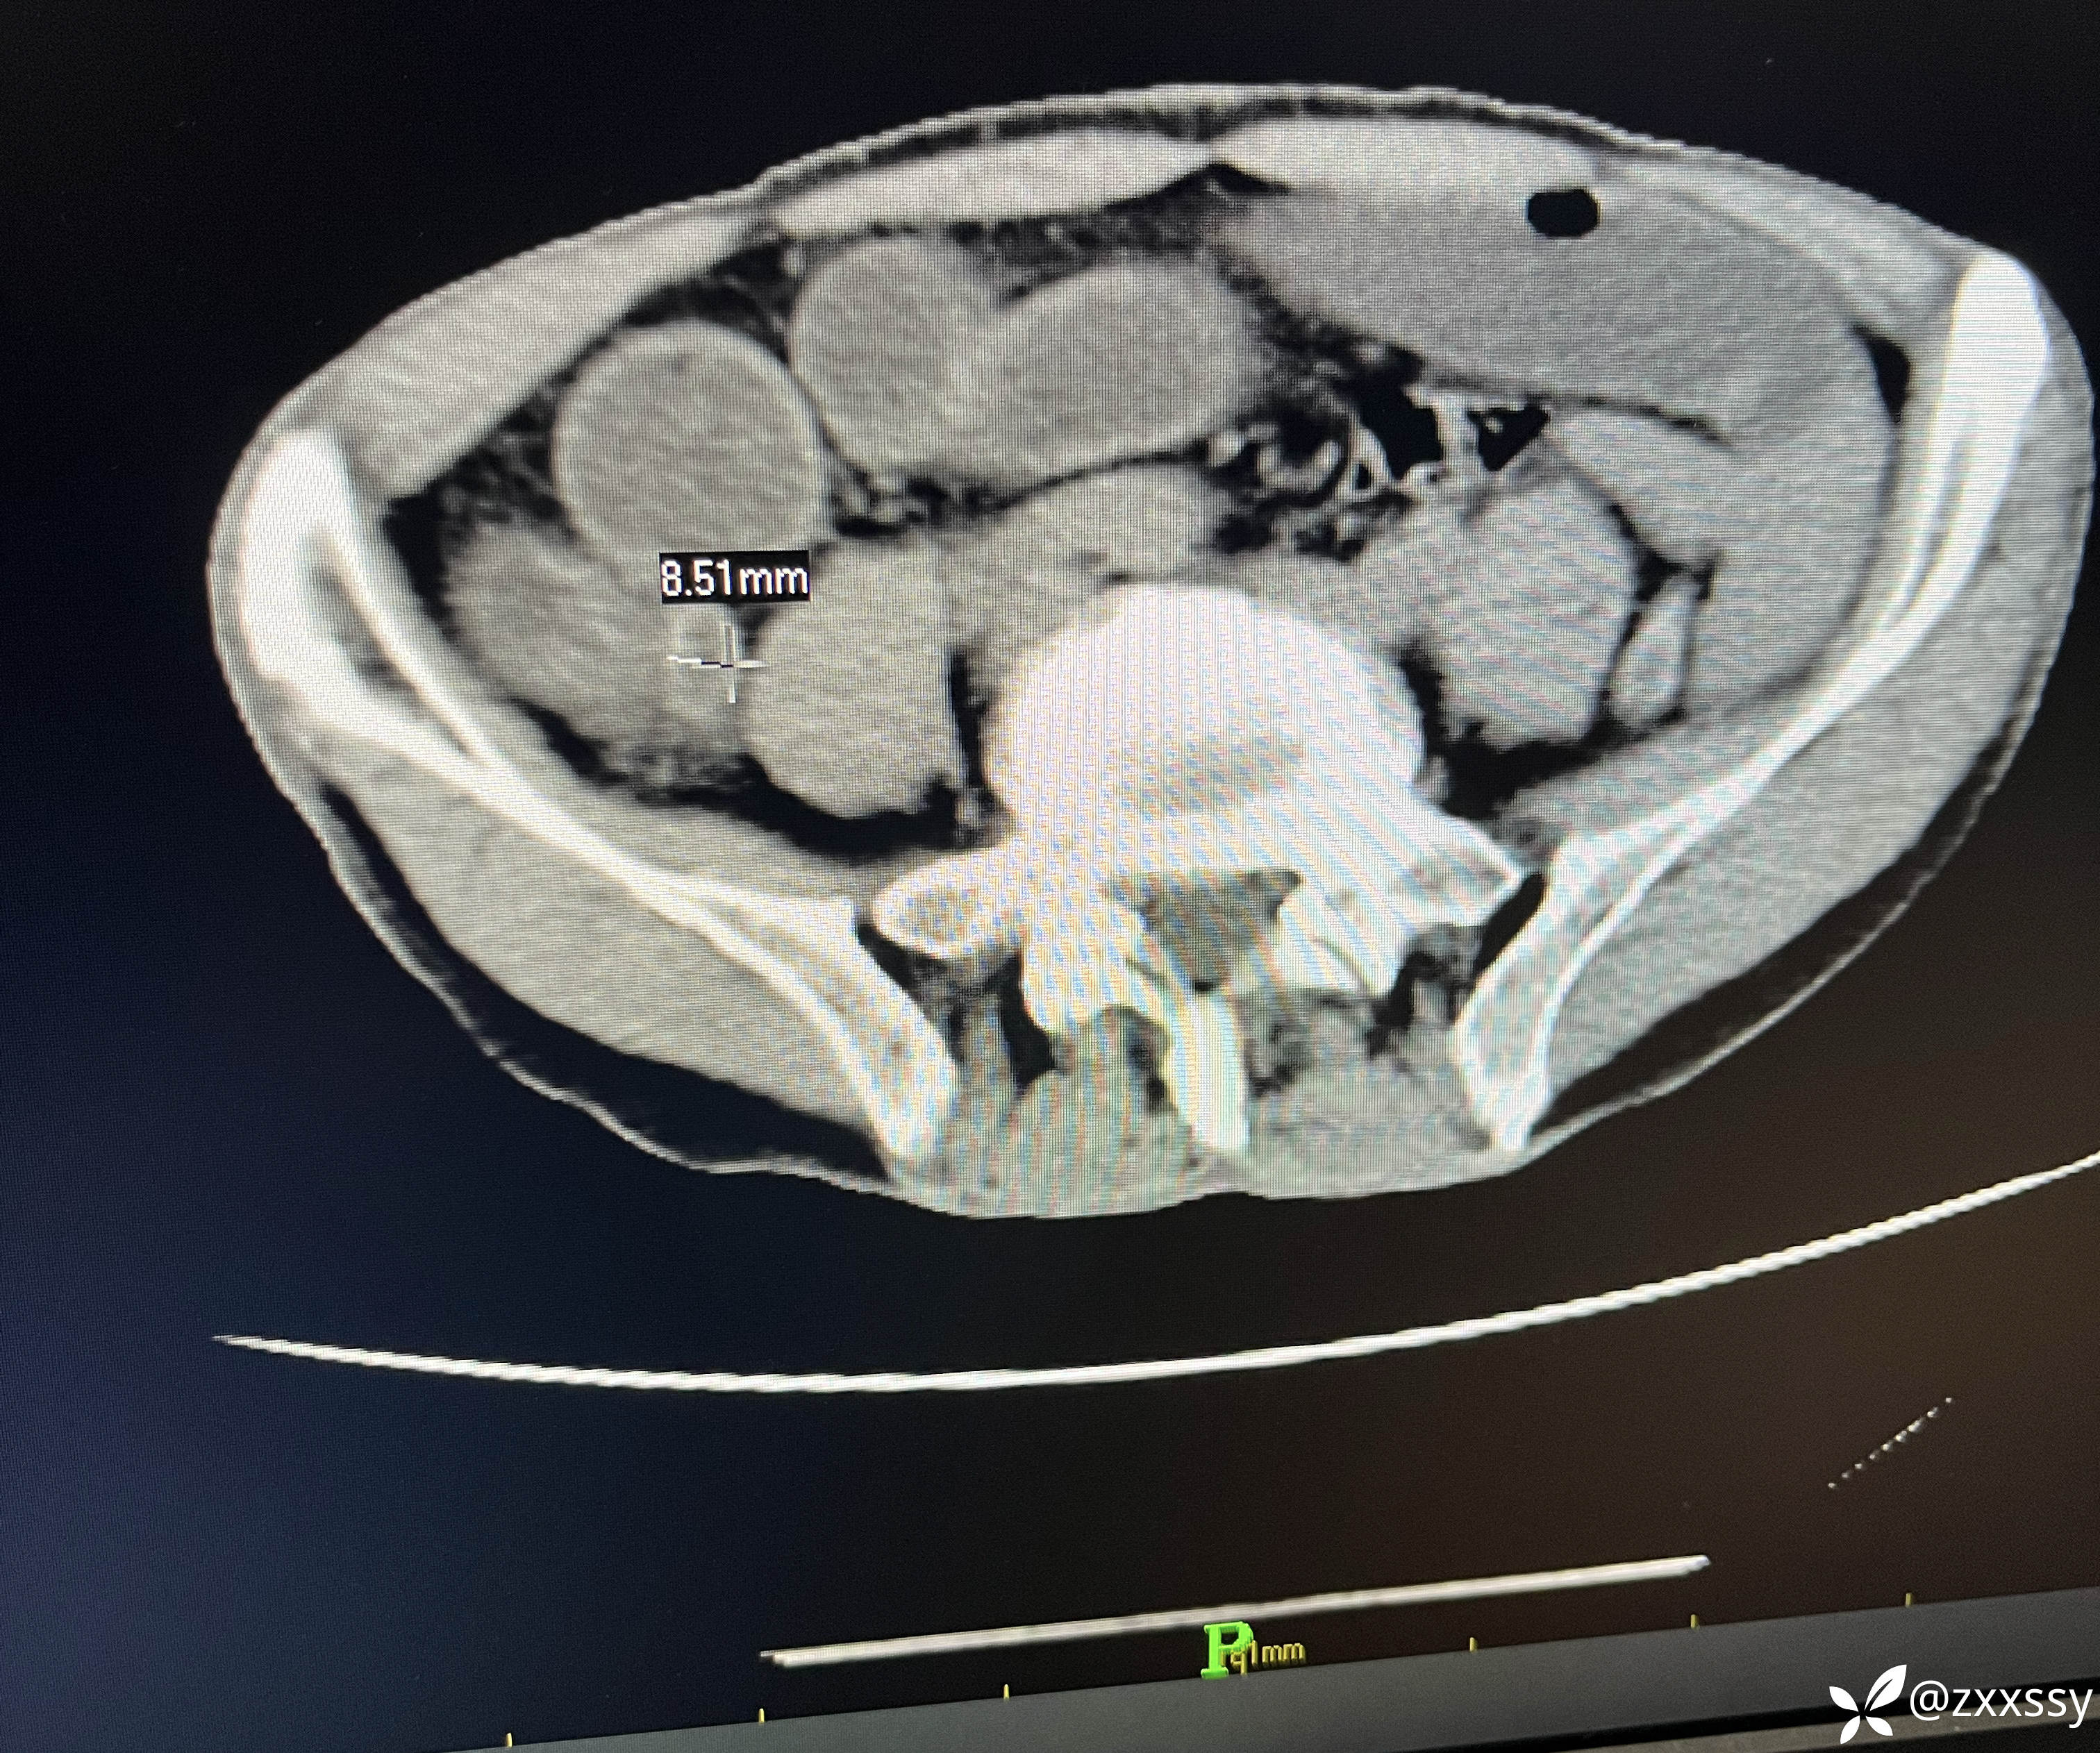

阑尾尖端粪石

临床诊断:1.急性阑尾炎并粪石形成;2.小肠梗阻;3,回盲部管璧不规则增后,周围淋巴结多发(回盲部肿瘤?);4.盆腹腔积液。